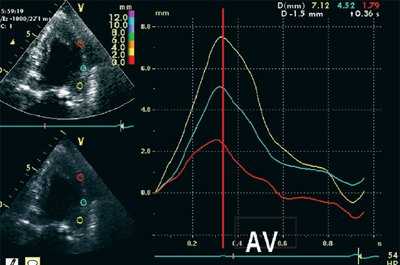

На рис. 3-5 приведены различные варианты ПСУ у больных с постинфарктным кардиосклерозом.

![Норма - формы кривых движения миокарда]()

![Седло - формы кривых движения миокарда с постинфарктным кардиосклерозом]()

б) При постинфарктном кардиосклерозе.

![Ступень - формы кривых движения миокарда с постинфарктным кардиосклерозом]()

в) При постинфарктном кардиосклерозе.

"Седловидная" и "ступенчатая" формы движения обусловлены наличием постсистолического смещения миокарда, превышающего по амплитуде максимальное систолическое смещение.

Вертикальная линия (AV) на рис. 3-5 соответствует времени закрытия аортального клапана. На представленных графиках также отмечается наличие базально-верхушечного градиента (снижение пиковых миокардиальных скоростей, продольного систолического смещения и деформации от основания к верхушке левого желудочка).